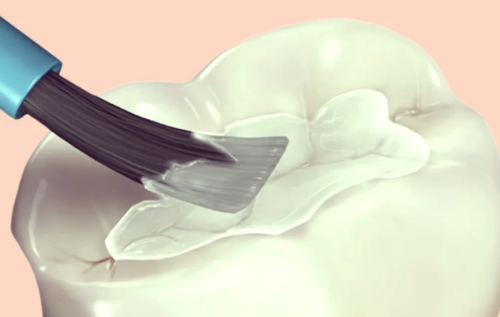

9. 儿童窝沟封闭:50 - 200元